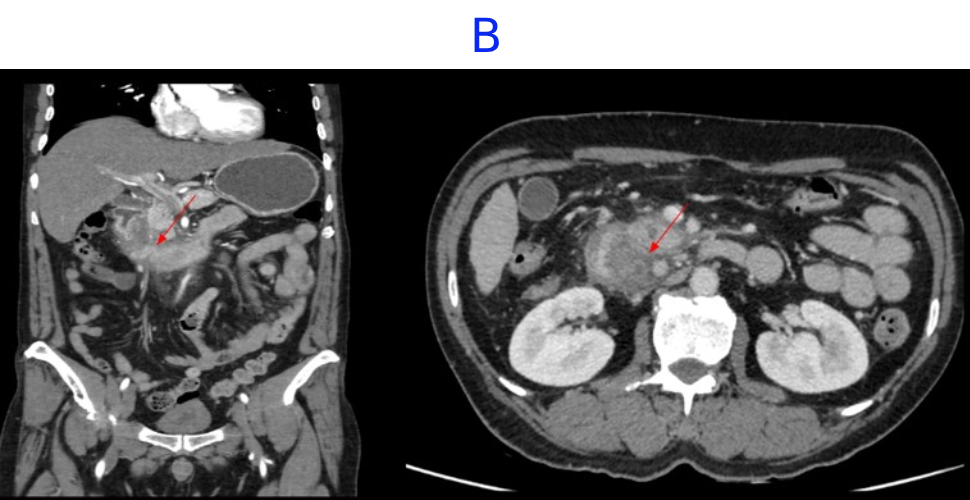

- B. Few hypoenhancing areas within the medial wall of duodenum. Uncinate process of pancreas appears oedematous.